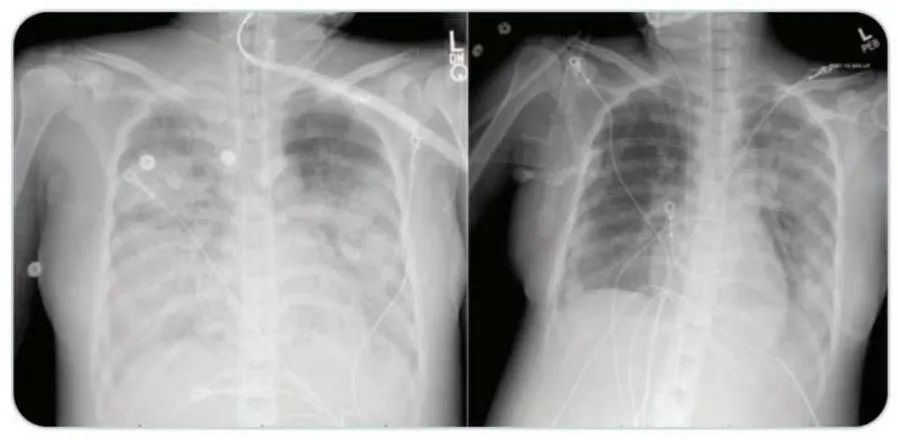

该患者本来是40多岁的健康女性,因呼吸道感染而入院,胸部CT影像显示为获得性肺炎。医院立即将其进行隔离以防止感染传播。入院24小时内,她的呼吸状况恶化。医院给她插管,并给予抗生素,包括利奈唑胺,哌拉西林-他唑巴坦和阿奇霉素治疗。

该患者在接受瑞德西韦(Remdesivir)治疗后,患者病情好转,需要的呼吸机支持明显减少,血氧水平和胸部CT检查结果好转。在入院治疗十四天后,已经可以撤离机械通气。 目前患者已出院,正在在家中康复。